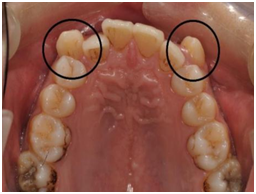

上面两张照片里圈出来的牙齿就是俗称的“虎牙”,他其实是异位萌出的尖牙,它的出现与牙齿的萌出顺序以及牙齿排列的拥挤程度有关。尖牙往往是最后萌出的牙齿,牙齿排列越拥挤,尖牙成为“老虎牙”的几率也就越大。“虎牙”的存在不但影响美观,还不能有效发挥尖牙的撕扯功能,咀嚼过程中还可能咬伤嘴唇。

尖牙在面部美观和咀嚼功能上作用巨大,虎牙即使站错队,也不建议因一时冲动而拔掉。